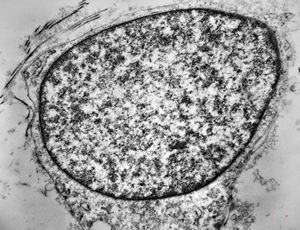

M,2y. | myopathy - regenerating muscle cell